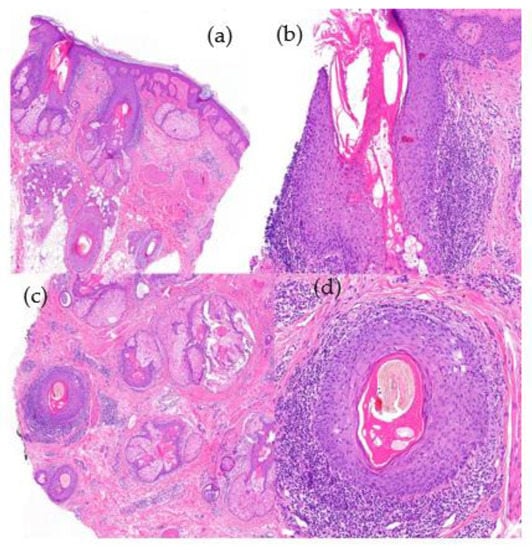

- Histological Features (Figure 11):

- -

- Hyperkeratosis predominantly involving the infundibulum of the hair follicle.

- Vacuolar interface dermatitis; primarily affects the follicular epithelium and the dermoepidermal junction.

- Presence of isolated Civatte’s bodies [51].

- Superficial and deep perivascular and periadnexal lymphocytic infiltrate.

- Pigmentary incontinence.

- Increased dermal mucin.

- Immunofluorescence (IFD) testing reveals a positive lupus band characterized by granular deposits of IgG, IgM, and/or C3 at the dermoepidermal junction and follicular epithelium.

- Orcein staining reveals elastic fiber destruction throughout the entire dermis (advanced stages).

- Histological Features (Figure 12):

- Hypergranulosis and infundibular hyperkeratosis.

- Lichenoid interface dermatitis observed in the follicular epithelium, specifically the infundibulum and isthmus, as well as at the dermoepidermal junction.

- Lymphocytic infiltration of the follicular epithelium.

- Presence of abundant Civatte’s bodies (necrotic keratinocytes) within the follicular epithelium (detectable through positive cytokeratin staining) [51].

- Concentric perifollicular fibrosis (advanced stages) with retraction clefts.

- Orcein staining reveals a cradle cap scar centered around the follicle.

- Immunofluorescence (IFD) testing is positive for IgM deposits in the follicular epithelium.

- IFD: the abundant Civatte bodies are frequently positive for IgM.